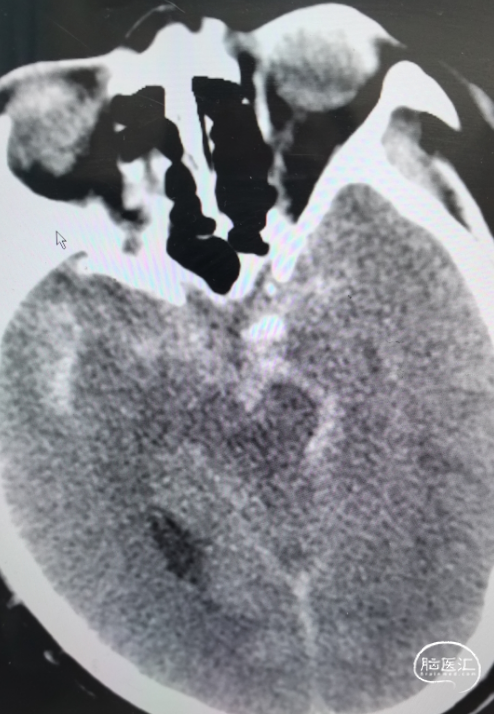

影像信息

头颅CT显示:额叶蛛网膜下腔出血。

完善头颅CTA显示:前交通动脉瘤、左侧大脑中M1段末端动脉瘤。

DSA造影确认前交通动脉瘤、左侧大脑中M1段分叉部动脉瘤。

前交通动脉瘤5.94mm*4.12mm,瘤体呈分叶状。

患者右侧大脑前发育纤细;后循环血管无明显异常。